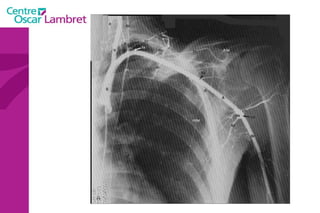

Artères sous-clavières  : l’une à droite et l’autre à gauche. La droite naît du tronc brachio-céphalique moins longue que la gauche, elle se dirige obliquement en haut et en dehors.  La sous-clavière gauche, au contraire, naît directement de l’aorte, remonte verticalement en haut. Arrivées au niveau de la première côte, ces deux artères présentent la même disposition, deviennent horizontales, passent entre les deux muscles scalènes et prennent le nom d'axillaires.

L’artère vertébrale  : Elle naît de la sous-clavière pré-scalénique et chemine verticalement sur 25 cm environ.  On lui décrit 4 segments. L’appareil circulatoire

L’artère mammaire interne  : naît de la face inférieure de la sous-clavière, un peu en dehors de la vertébrale. Elle épouse la partie antérieure du dôme pleural et descend verticalement à la face profonde du plastron costal à 1 ou 2 cm en dehors du bord latéral du sternum.  L’appareil circulatoire